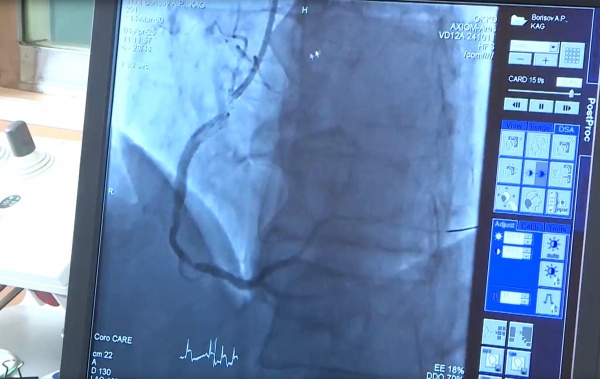

Врач-кардиолог диагностировал острый инфаркт. Пациента экстренно госпитализировали. Для оценки состояния сосудов была проведена коронарная ангиография.

Хотя ситуацию усложнял нетипично большой диаметр артерии, бригада врачей успешно провела операцию.